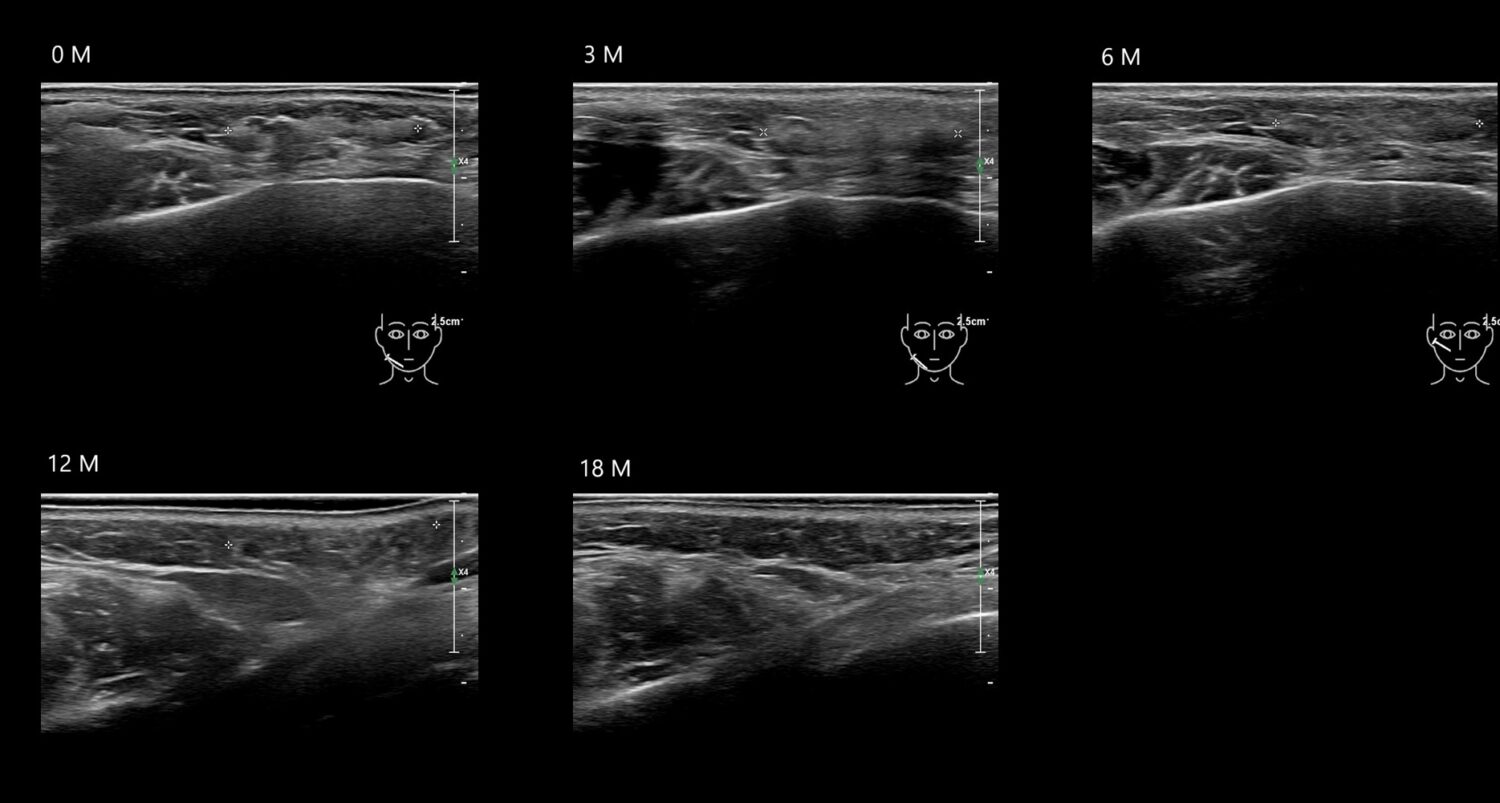

Filler library